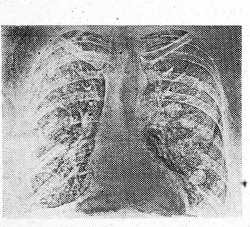

Больной К., 53 лет, страдает неоперабельным раком желудка. 18/УП 1978 г. рентгенографией органов грудной клетки установлено следующее. Легкие: слева в среднем поле определяются три круглые, монетообразные тени диаметром от 2,5 до 1,5 см, предположительно метастазы опухоли; в нижнем легочном поле выявляются еще две подобные тени, одна диаметром 2 см, вторая с менее четкими контурами, диаметром 1 см, расположена латеральнее. С той же стороны в проекции переднего конца II ребра и во втором межреберье латерально отмечаются еще две тени диаметром 6 и 8 мм. Оправа заметна округло-овальная тень на фоне переднего. отрезка II ребра. В среднем и нижнем легочных полях, кроме резко выраженного усиленного и деформированного легочного рисунка, изменений выявить не удалось (рис. 2).

Рис. 2. Электрорентгенограмма легких больного К. Объяснение в тексте.

На пленочной рентгенограмме картина слева идентична с данными ЭРГ, справа тень на II ребре более отчетлива, усиление и деформация легочного рисунка выражены в меньшей степени, на фоне его обнаружены еще 6 округлых теней. Одна диаметром 1 см локализуется в среднем легочном поле и четыре диаметром 3 и 4 мм в нижнем, пятая тень диаметром 5 мм — в третьем межреберье по среднеключичной линии (рис. 3). При повторном анализе ЭРГ тень в среднем поле удалось отдифференцировать на фоне обильного легочного рисунка, но тени в нижнем поле оказалось невозможным отличить от деталей деформированного рисунка (рис. 2).